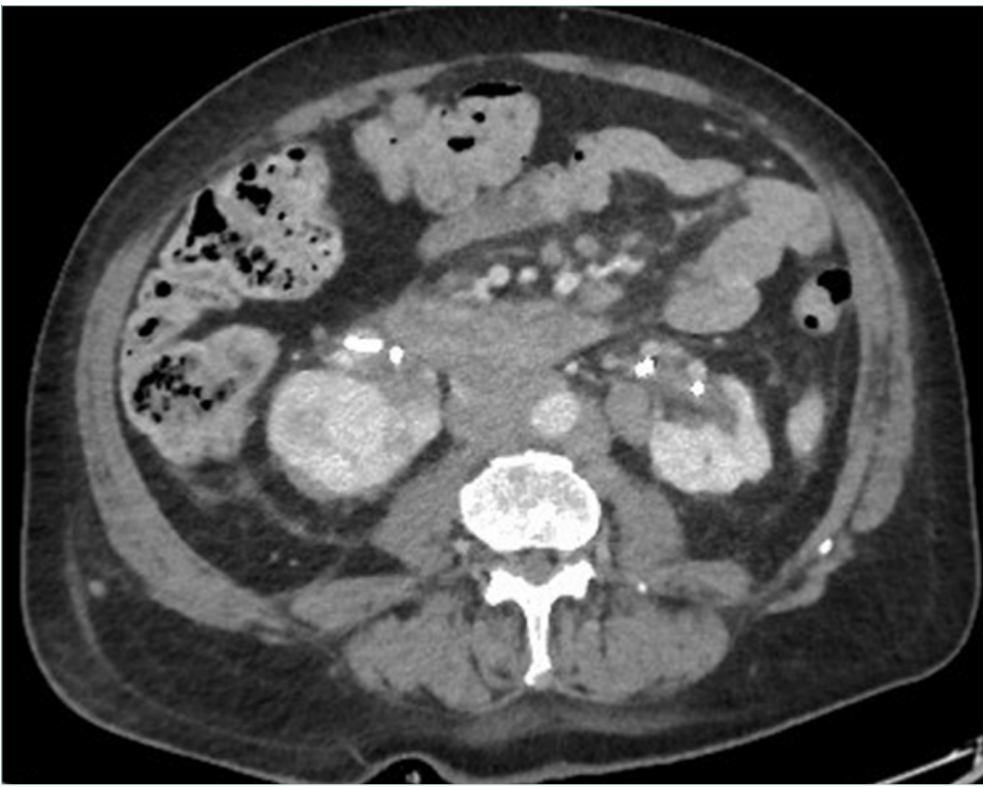

Computed tomography (CT) venography is an easily available and the most commonly used imaging technique as it can be performed through peripheral venous access with injection of 150 mL of iodinated contrast agent with acquisition at 90 and 120 seconds4 (Figures 2 and 3). According to a recent Delphi consensus, it should be the first-line imaging technique.5

Figure 3. Complete occlusion of the infrarenal inferior vena cava due to lymph nodes from bladder cancer; presence of bilateral nephrostomy due to bilateral ureteral compression.

Both techniques can depict the tumoral and vascular lesion(s). CT angiography and CT venography (or MRV) are mandatory in order to look for tumor vascularization, IVC status (obstruction or occlusion [Figures 2 and 3]) and collateral pathways. According to O’Sullivan, CT venography should be proposed in all cancer patients with lower-limb edema.2